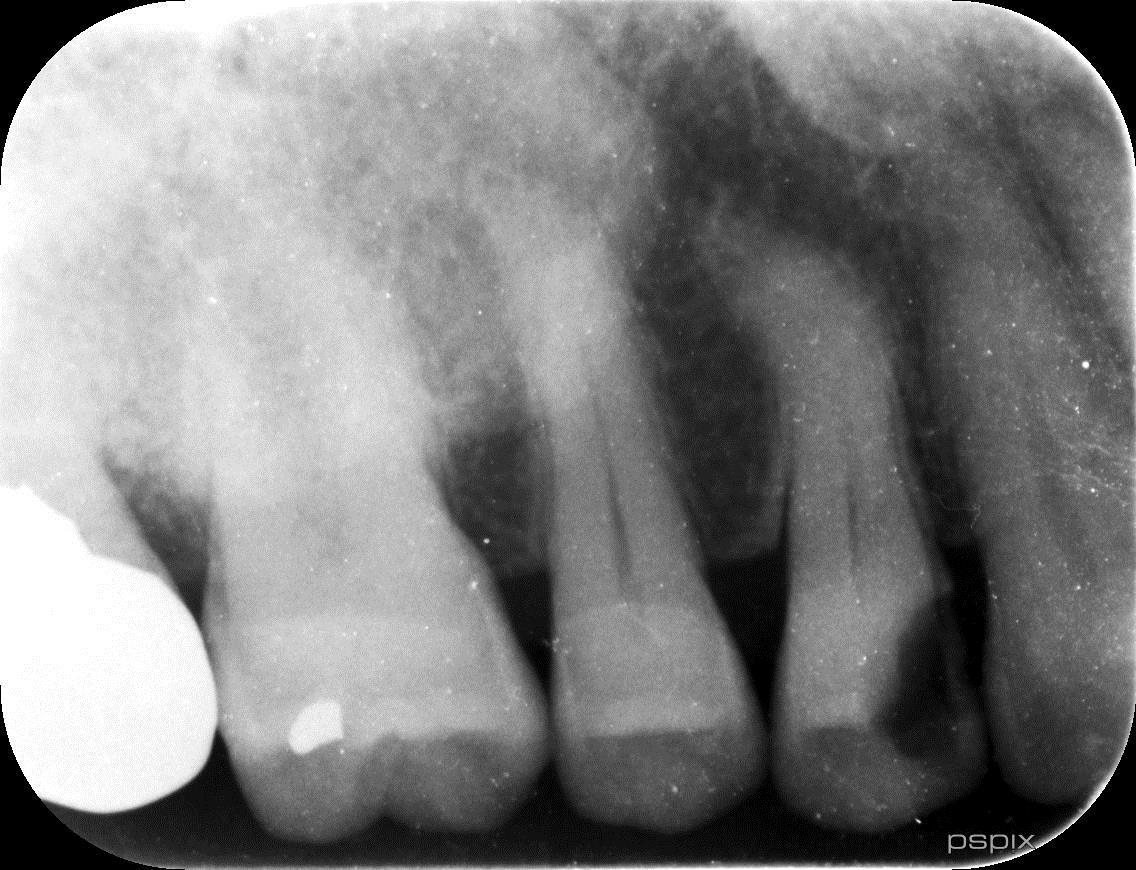

必要に応じてCT撮影を実施(根管形態の確認や病変の確認の為)

歯の根の形態は非常に複雑で、通常のレントゲンでは確認できない場合があります。CT撮影を行うことで、根管の本数や形、病変の広がりを立体的に把握し、的確な治療計画を立てます。